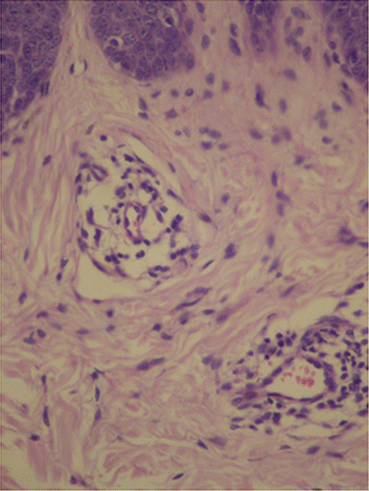

Fig. 3.10

Vascular proliferation and vasodilation in the superficial dermis. Archives of the Ambulatório de Psoríase, Pontifícia Universidade Católica de Campinas

Fig. 3.11

In the superficial dermis, capillaries are increased in number and size, and show a tortuous appearance. Archives of the Ambulatório de Psoríase, Pontifícia Universidade Católica de Campinas

Fig. 3.12

Acanthosis, elongation of dermal papillae, hyperkeratosis with parakeratosis, and thinning of the suprapapillary region. Archives of the Ambulatório de Psoríase, Pontifícia Universidade Católica de Campinas

Anatomopathology

In psoriasis, histopathological findings are nonspecific but very characteristic, and may be found in other dermatological diseases, such as in Pityriasis Rubra Pilaris and Lichen Simplex Chronicus [12]. In initial lesions, vascular proliferation and superficial vasodilation are observed in the dermis (Fig. 3.10). The perivascular infiltrate is composed of lymphocytes and macrophages. With plaque development, this infiltrate becomes a mixture of lymphocytes, macrophages and neutrophils, with neutrophils and lymphocytes migrating towards the epidermis. Vascular alterations become even more evident, with an increase in the number and size of capillaries, as well as the acquisition of a tortuous appearance (Fig. 3.11) [13]. In the epidermis, there is an increase in the spinous layer (acanthosis), as seen by the regular elongation of the dermal papillae and epidermal cones (Fig. 3.12). The suprapapillary region becomes thinned and the granular layer may be reduced or absent (hypogranulosis or agranulosis) [12]. In the corneal layer, hyperkeratosis with parakeratosis (because of the increase in nucleated keratinocytes) is evident. Neutrophils that migrated towards the epidermis gather forming Munro’s microabscesses in the corneal layer, and spongiform pustules of Kogoj in the spinous layer [12].